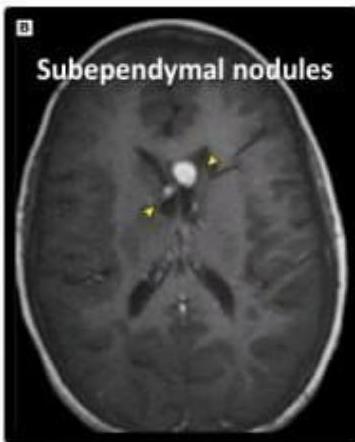

- Subependymal Nodules: Calcified nodules adjacent to lateral ventricles (Hamartomas).

Subependymal calcification: